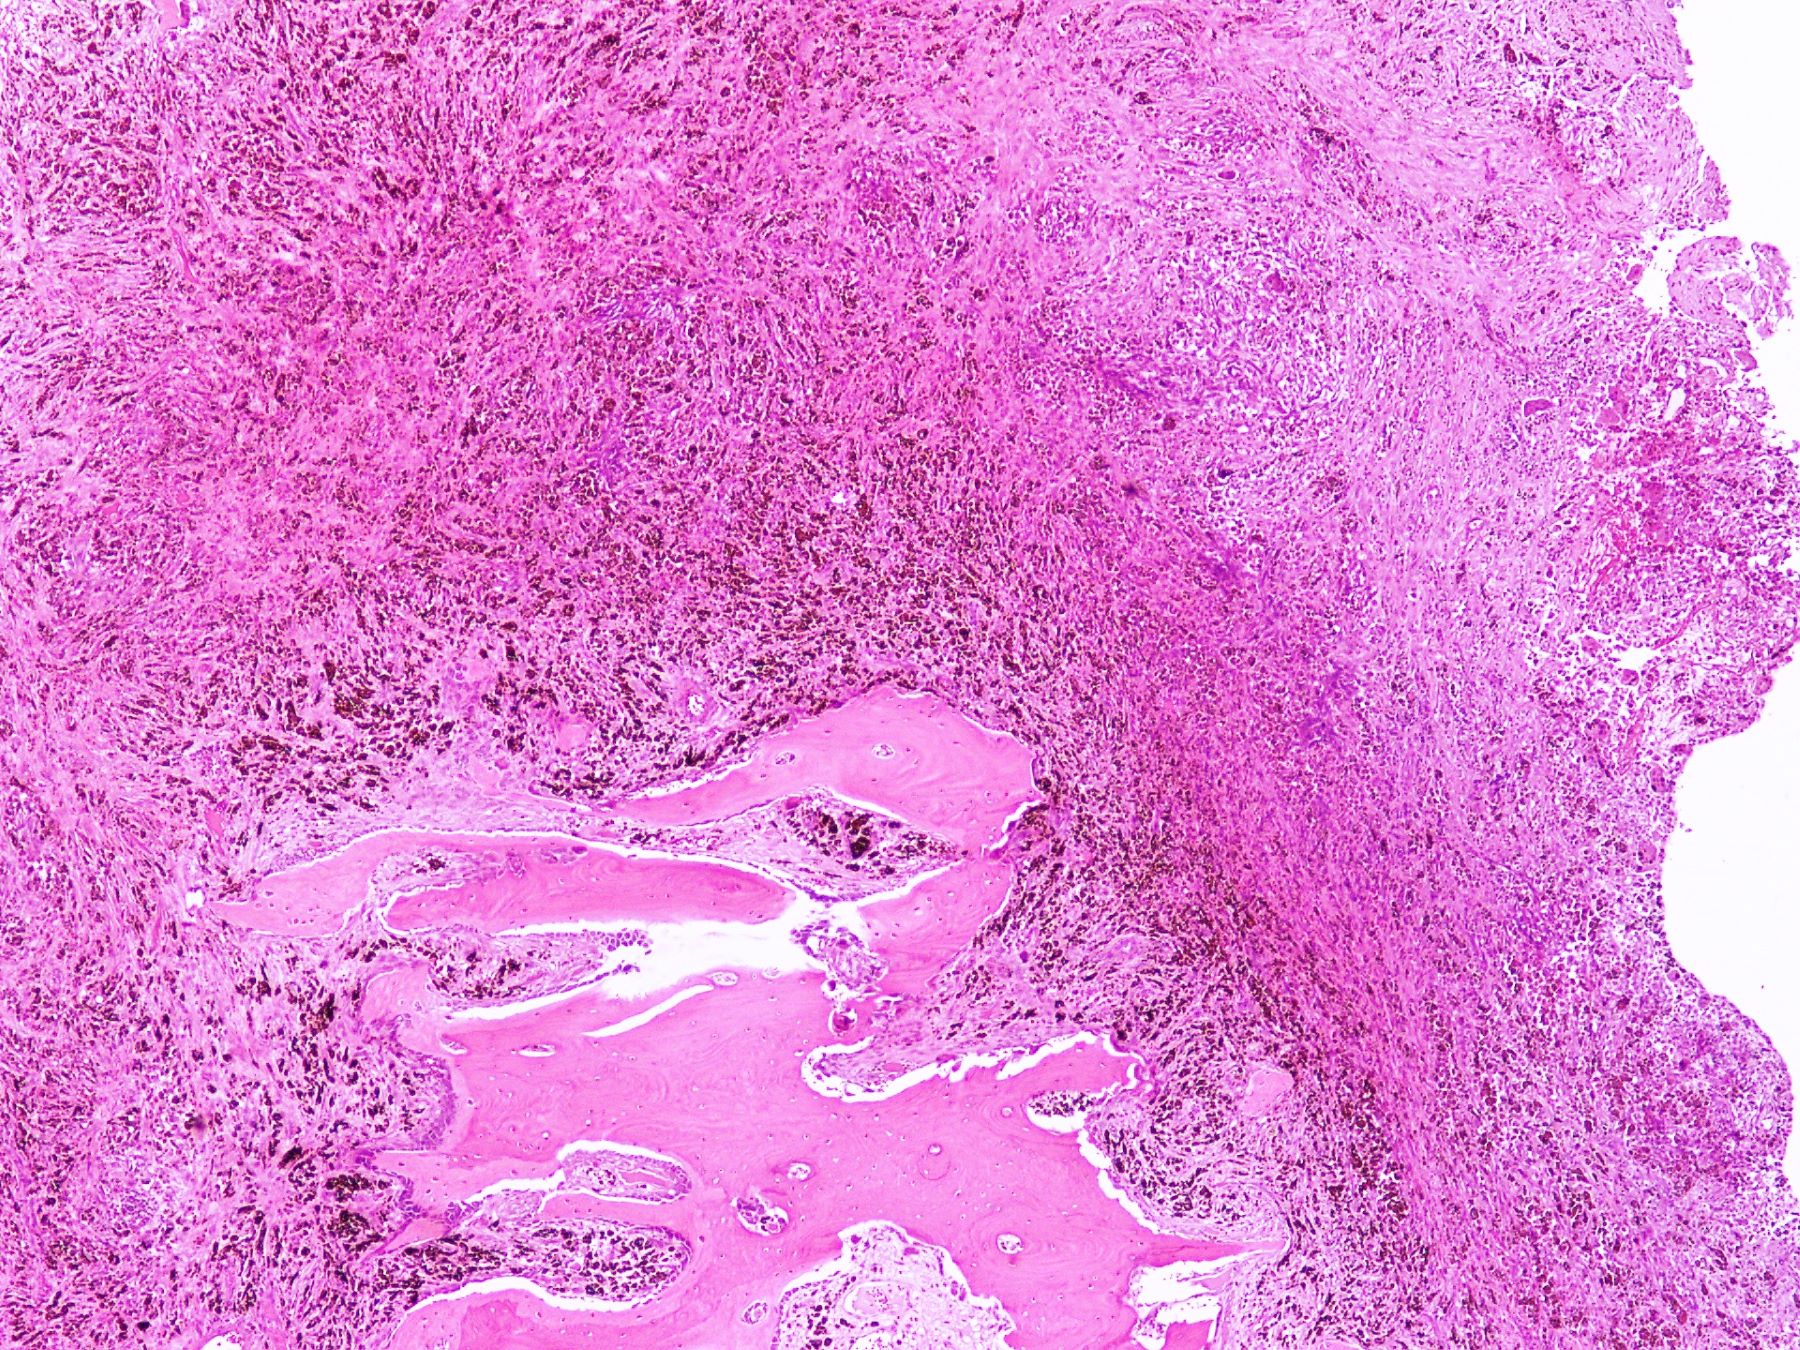

Microscopic (histologic) description

- Lobular pattern composed of groups and clusters of osteoclast-like multinucleated giant cells

- Vascular fibroblastic stroma

- Hemorrhage and hemosiderin deposits

- Tunneling resorption of adjacent uninvolved bone (J Int Oral Health 2015;7:50)

Microscopic (histologic) images

A 50 year old woman presented with a swelling on the right side of her face that gradually increased in size over last 3 years. It was associated with pain, trismus and inability to open her right eye. She also had history of frequent headaches, abdominal pain and renal stones. Xray revealed a lytic lesion within the right mandible. Incisional biopsy was performed and microscopic examination revealed a lesion (shown above). The most likely diagnosis is

B. Brown tumor of hyperparathyroidism. The photomicrograph shows a lesion composed of bony trabeculae showing resorption along with scattered osteoclast-like giant cells in a vascularized spindled stroma. These microscopic findings with above mentioned clinical and radiological features are characteristic of brown tumor of hyperparathyroidism. Aneurysmal bone cyst affects young adults and shows large blood filled spaces with intervening septae containing fibroblasts and giant cells. Central giant cell granuloma produces radiolucent lesions in children and young women and shows osteoclast-like giant cells near hemorrhagic areas, cellular vascular and fibrous stroma and new bone formation at edge of lesion. Cherubism shows bilateral involvement of mandible and maxilla in young individuals and histology is similar to central giant cell granuloma. Giant cell tumor rarely affects mandible and shows uniform distribution of osteoclast type giant cells among mononuclear cells.